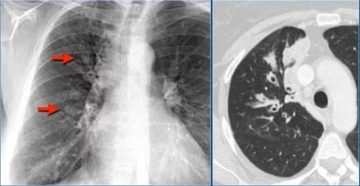

Множественные очаги в легких Компьютерная томография (кт) — это один из методов исследования человеческого тела…